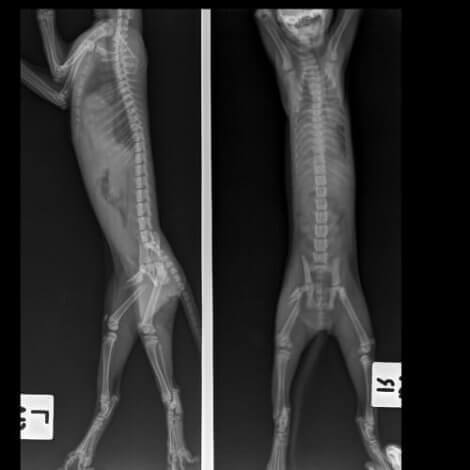

Det er viktig å påpeke viktigheten av å få stilt en riktig diagnose slik at katten din ikke ender opp med permanente muskel- eller nervesykdommer. Veterinæren din vil gjennomføre en fullstendig undersøkelse av katten din for å prøve å finne den nøyaktige årsaken til problemet.

Diagnostiseringen kan kreve noen spesielle tester som ofte involverer én eller flere av følgende:

- Røntgen

Kattens alder, skadehistorie, om problemet er akutt eller kronisk, alvorlighetsgraden av deres halthet, og hvor mange bein det er snakk om er alle faktorer som kan bidra til å peke på kilden til problemet.